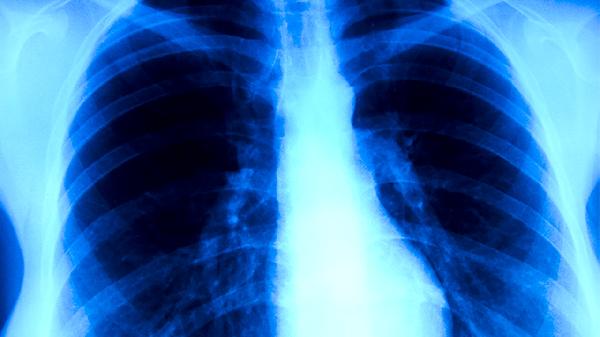

引发肺癌的有害因素主要有长期吸烟、二手烟暴露、职业性致癌物接触、空气污染以及遗传易感性等。肺癌的发生通常是多因素共同作用的结果,其中吸烟是最主要的可预防危险因素。